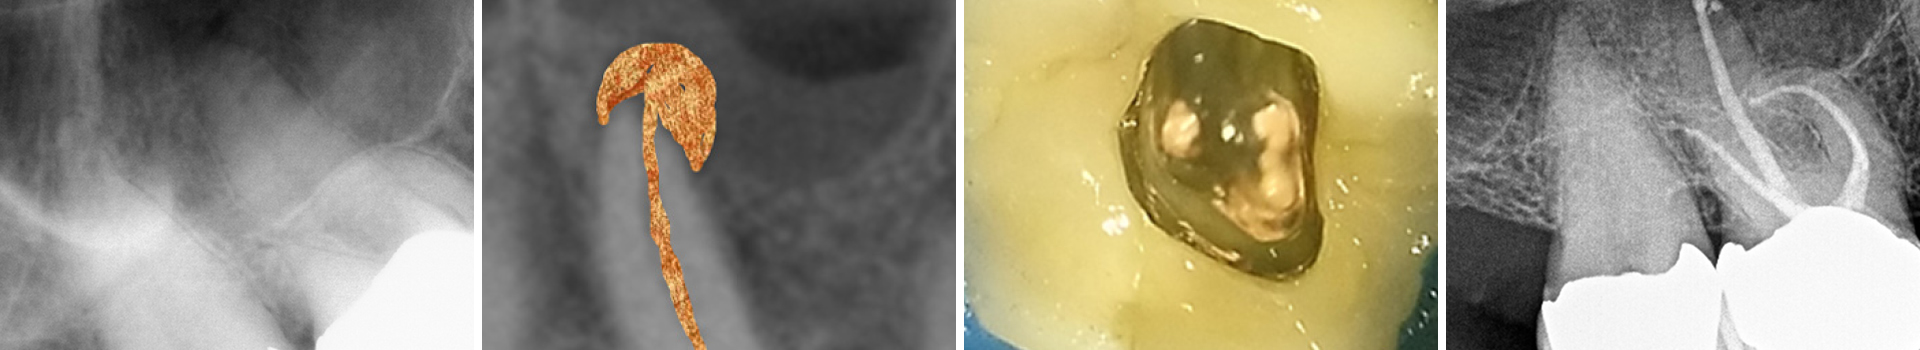

Abbildung 3a

Obliterierte bukkale Kanäle...

Abbildung 3b

...und eine starke Krümmung mesiobukkal.

Abbildung 4

Die klassische Aufbereitung bei gekrümmten Kanälen erfolgt durch Erweiterung des Kanaleingangs mit konventionellen Stahlbohrern (Gates Glidden) oder NiTi Introfeilen mit höherer Konizität, was zu einer unnötigen Entfernung von Dentin am Kanaleingang führt (oranger Bereich). Um diese zu vermeiden wurden die Kanäle mit wärmebehandelten Niti-Feilen der neuesten Generation (FKG RACE EVO) bei 1.000 rmp/ 1,5 N-cm aufbereitet.

Abbildung 5

Der maschinelle Gleitpfad wurde mit der RACE EVO 15.04 geschaffen und die Kanäle bukkal bis 35.04 und palatinal bis 50.04 präpariert.